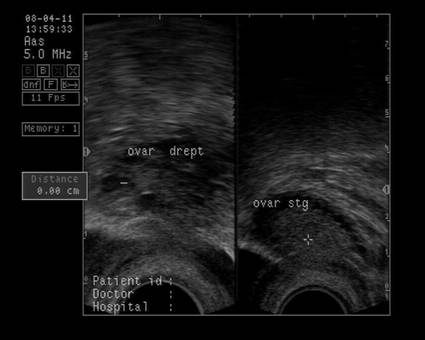

Ovarele. Sectiunea longitudinala directa, spre peretele lateral pelvin, la ecografia transvaginala, pune in evidenta ovarele cu forma elipsoidala. Acestea au structura ecografica relativ slab ecogena, in apropierea si sub vasele iliace.[5]